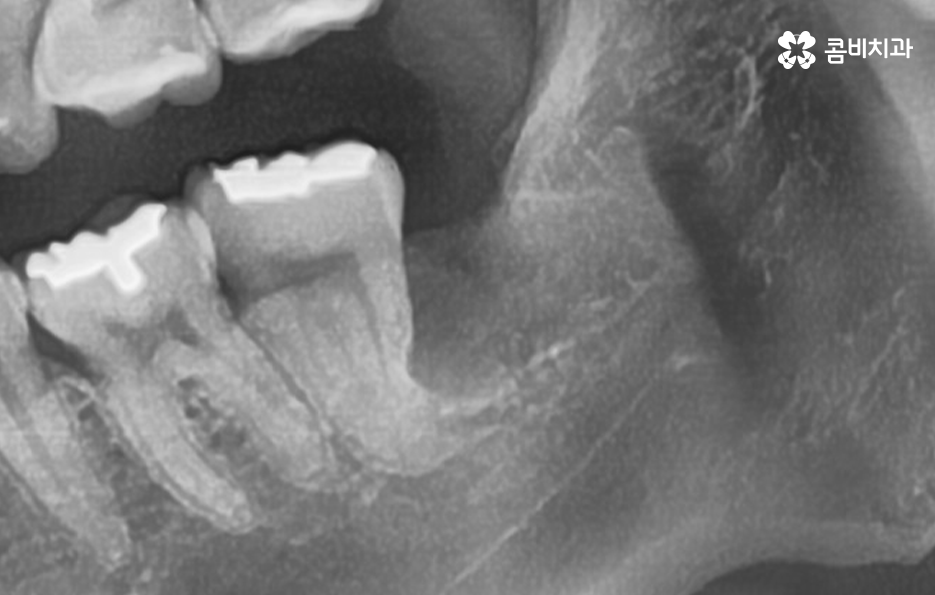

정상적으로 맹출된 사랑니가 아닌 사진에서 보시는 사랑니의 케이스처럼 어금니 부분으로 완전히 누워있는 사랑니의 경우에는 늦지 않게 발치 계획을 세우시길 권하고 있습니다

사랑니 발치에 대해 시점이 중요한 이유 중에 하나는 어금니와 인접하기 때문에 정상적인 위치와 방향으로 맹출된 사랑니라도 청결관리 문제로 인해 어금니에도 악영향을 주는 사례가 많기 때문인데 누워있는 사랑니의 경우에는 청결관리와 무관하게 어금니 손상을 일으키는 경우가 많기 때문에 미리 예방적으로 발치를 권하는 경우가 많이 있어요

누운 사랑니 발치를 미리 예방적으로 하면 좋은 이유는 어금니 방향으로 누워서 자라는 사랑니는 아무리 청결관리를 잘해도 보통 3,40대 이후에는 어금니를 썩게 만들고 어금니 충치가 심해져서 심한 경우 어금니 마저 발치하게 되는 경우가 많이 있는데요

누운 사랑니로 인해 인접한 어금니에 충치가 발생하기 더 쉬운 이유는 위 사진처럼 발치 후 사진을 보더라도 치아의 구조상 치아의 하단 부분은 단단한 법랑질이 아닌 상아질로 이뤄져 있기 때문에 누운 사랑니로 인해 세균이 좀더 침투하기 쉬운 상태라는 점도 누워있는 사랑니를 발치해야 할 이유 중 하나라고 할 거예요

위 사례 이미지의 경우 그래도 다행인 점은 사랑니 발치 시점이 늦지 않아서 완전 누운 사랑니 임에도 큰 고생은 안했던 사례라고 본다면 아래 환자분의 사례는 이미 사랑니 뿐 아니라 어금니 까지 충치가 심해진 사례라고 할 수 있는데요